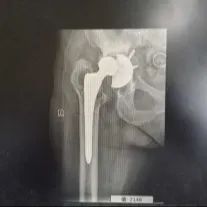

02对股骨柄假体进行了截骨处理。

最终,经过长达6个时15分的鏖战,手术取得圆满成功,经术后康复训练,鞠婆婆如今已能自由行走,康复出院。